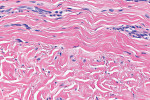

The histologic evaluation showed collagen that aligned horizontally, in a mostly parallel nature, to the superficial epithelium in both the ungrafted (Figure 10 and Figure 11) and grafted (Figure 12 through Figure 15) biopsy sites. In the grafted specimens, a clear demarcation at the interface of the native tissue and the implanted tissue was present. The implanted tissue, which was characterized by dense bands of disorganized collagen matrix, appeared well incorporated and without inflammatory cells. The Verhoeff's stain demonstrated the presence of numerous darkly stained elastin fibers in the implanted tissue that were inconspicuous in the native tissue.

The H&E and Verhoeff's stains allowed the collagen architecture of the native tissue to be clearly distinguished from that of the implanted tissue. The superficial native tissue exhibited collagen fibers that aligned parallel to each other and the epithelium, whereas the implanted tissue exhibited collagen fibers that appeared disordered. The implanted tissue, however, was markedly thicker than the overlying native tissue. Verhoeff's stain, which stains elastin fibers, has been used to identify implanted ADMs in grafted GRD sites.1,4,15 In this case, the abundant darkly stained elastin fibers in the grafted specimen indicate that the hydrated ADM was incorporated and not absorbed or exfoliated. The absence of observable inflammatory cells indicated that the implanted hydrated ADM was immunologically inert.